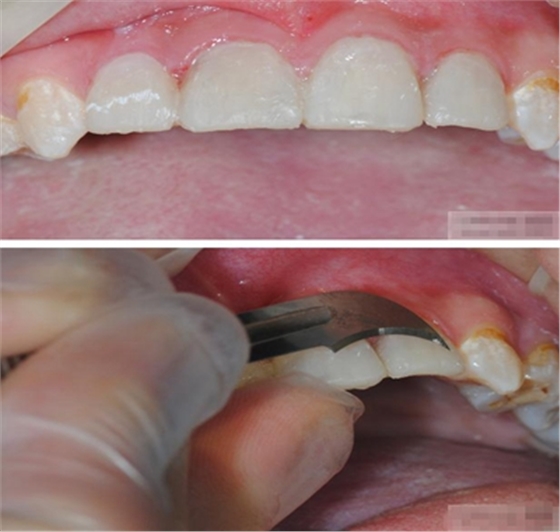

修整纖維樁長度

取出纖維樁,按所需長度裁截纖維樁 在有水條件下 用切割砂片或車針截取纖維樁,切勿使用鉗子,剪刀或鑷子以免破壞樁的結(jié)構(gòu)

涂布硅烷偶聯(lián)劑

涂布粘接劑

將樹脂粘接劑均勻涂抹在根管、牙體的粘接面以及纖維樁表面,涂抹兩遍

粘接

將調(diào)好的樹脂水門汀用口內(nèi)注射頭送入根管

將纖維樁表面涂滿調(diào)好的樹脂水門汀,安放在根管內(nèi)就位,保持壓力10秒